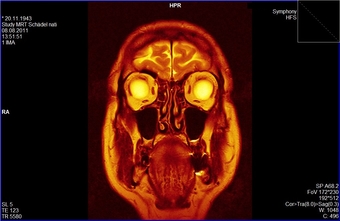

MRT-Aufnahme: Kopf eines 68jährigen Mannes

Die Magnetresonanztomographie (MRT) ist ein bildgebendes Verfahren, das vor allem in der medizinischen Diagnostik zur Darstellung von Struktur und Funktion der Gewebe und Organe im Körper eingesetzt wird. Hier zu sehen ist die MRT-Aufnahme des Kopfes eines 68jähigen Mannes. Es gelten die Nutzungsbedingungen der Mediothek und Pixiothek.